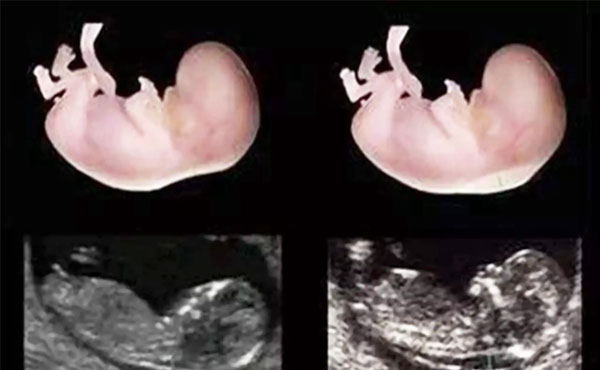

nt是指胎儿的颈部透明层,这种检查在临床上我们又叫做颈后透明带扫描,采用的方式是通过B超手段来测量胎儿颈部皮肤最厚的部位。假如超声波的分辨率比较高,能给胎儿的颈后透明层检测出有效厚度,NT的厚度不同,提示胎儿染色体异常的风险值不同,NT厚,胎儿的染色体异常风险高。NT薄,胎儿的染色体异常风险低。通常nt值小于2.5cm,说明胎儿正常的可能性比较大。而nt检查的最佳时间是在孕11-14内进行检测,虽然nt检测是孕早期的一项非常重要的检查项目,但一定要在正规医院进行检查,并且在后期要按规定进行定期产检。